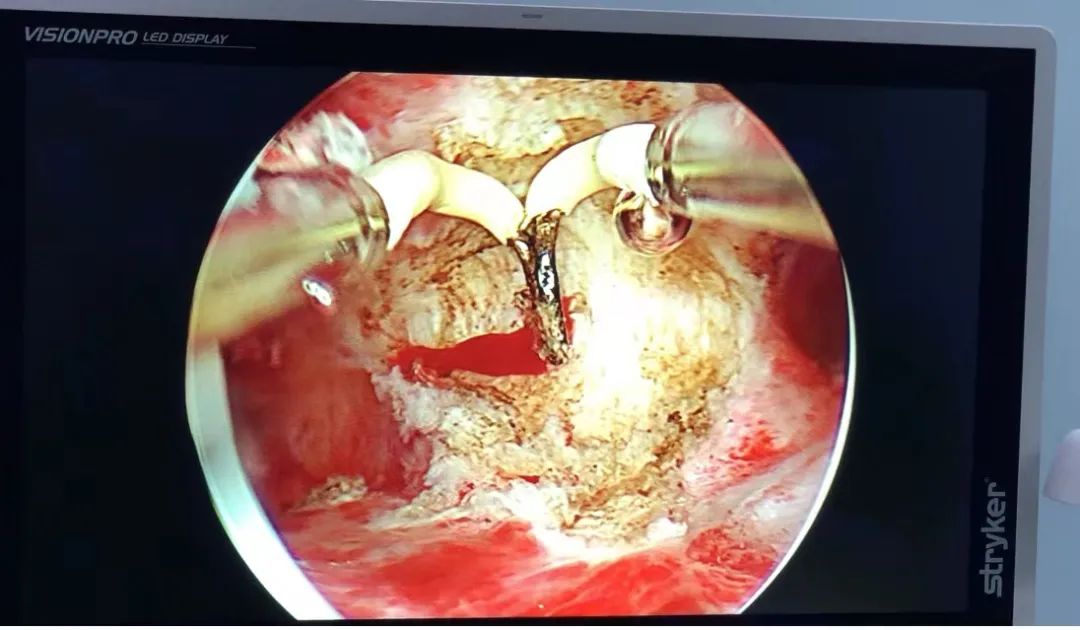

结合实际情况,为了创造更好的生育条件,减少自然流产,妇产科主任建议行宫腔镜下纵隔切术+双侧输卵管疏通术,手术非常成功,术后患者状况良好。